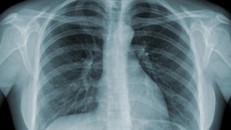

Ca tử vong thứ 81 do COVID-19 30/06/2021 18:16 Chiều 30/6, Tiểu ban điều trị Ban Chỉ đạo Quốc gia phòng chống dịch COVID-19 thông báo ca tử vong thứ 81 là bệnh nhân nam 61 tuổi ở TP Hồ Chí Minh do COVID-19 có tiền sử lao phổi

Cô gái chỉ còn 1/1.000 cơ hội sống vì di chứng lao 10/06/2019 14:24 Nữ bệnh nhân có tiền sử mắc lao phổi cách đây 2 năm, đã được điều trị khỏi bệnh. Di chứng do lao để lại khiến cô phải đối mặt với "thần chết".